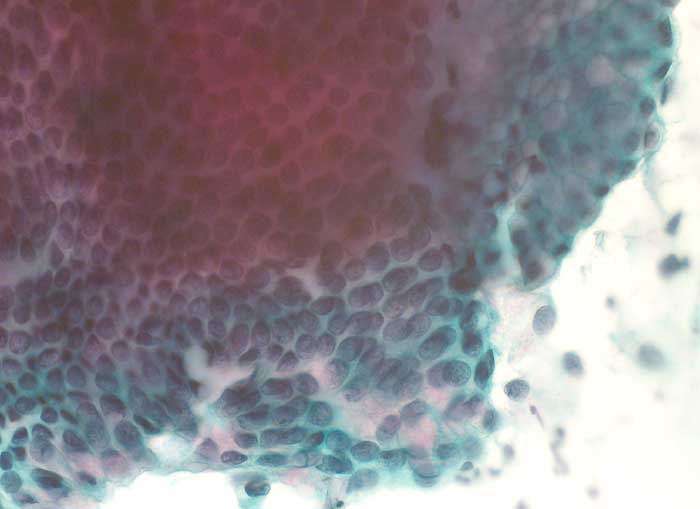

g/ Adenocarcinoma in situ der Zervix uteri

Adenocarcinoma in situ der Zervix uteri

Die Ausstriche des ACIS sind zellreich und enthalten atypische Zylinderzellen mit grossen Kernen. Diese bilden flache Verbände, die in der Aufsicht ein Honigwabenmuster, bei seitlicher Betrachtung ein Palisadenmuster und eine Pseudostratifikation der Kerne erkennen lassen. Die Kerne sind im Vergleich zum normalen Zylinderepithel deutlich grösser und enthalten einen vergrösserten Nukleolus. Eine Hyperchromasie ist nicht immer vorhanden und das granuläre Chromatin ist regelmässig verteilt. Der zytologische Nachweis von atypischen Zylinderepithelien sollte histologisch weiter abgeklärt werden.